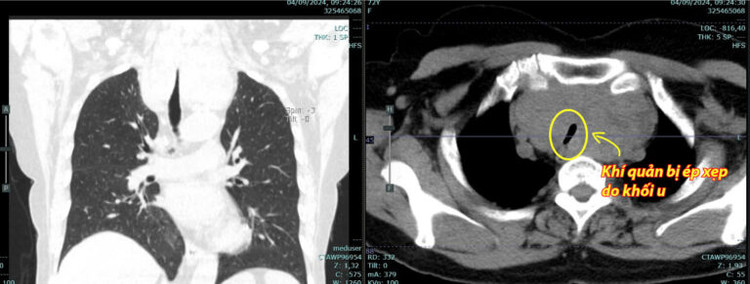

Quá trình phẫu thuật cho người bệnh D diễn ra tương đối khó khăn do khối u lớn lâu ngày, chèn ép vào khí quản đoạn ngực gây xẹp khí quản nhiều.

| Hình ảnh khối u bướu tuyến giáp thòng trung thất và khí quản bị ép xẹp do khối u Sau mổ khối u đã được lấy hết và khí quản đã bình thường - Ảnh BVCC |